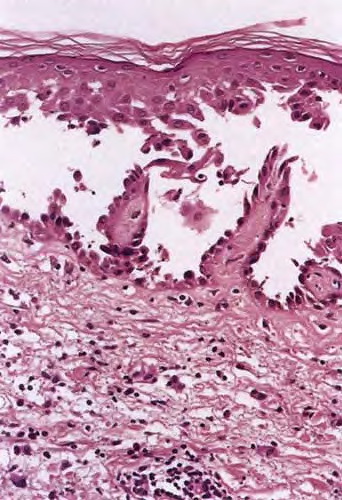

The earliest recognized change may be either eosinophilic spongiosis rarely or, more commonly, “spongiosis” in the lower epidermis . This spongiosis may actually represent the earliest manifestation of acantholysis rather than true spongiosis as defined earlier. Acantholysis leads first to the formation of clefts and then to blisters in a predominantly suprabasallocation . The intraepithelial acantholysis may extend into adnexal structures or occasionally be higher in the stratum spinosum. The basal keratinocytes, although separated from one another through the loss of attachment, remain firmly attached to the dermis like a “row of tombstones.” Within the blister cavity, the acantholytic keratinocytes, singularly or in clusters, have rounded condensed cytoplasm about an enlarged nucleus with peripherally palisaded chromatin and enlarged nucleoli. In some patients, there are varying quantities of antidesmoglein 1 and antidesmoglein 3 antibodies, leading to variable planes of acantholysis. There is little inflammation in the early phase of blister formation. If present, it is usually a sparse, lymphocytic perivascular infiltrate accompanied by dermal edema. However, if eosinophilic spongiosis is apparent, numerous eosinophils may infiltrate the dermis. The phenomenon of eosinophilic spongiosis occurs occasionally in other blistering diseases, particularly in their early phases, including acute contact dermatitis, pemphigus foliaceus, bullous pemphigoid, herpes gestation is, drug eruptions, spongiotic arthropod bite reactions, and transient acantholytic dermatosis. Several important changes ensue as the lesions age. First, a mixed inflammatory cell reaction consisting of neutrophils, lymphocytes, macrophages, and eosinophils may develop. Because of the instability of the blister roof, erosion and ulceration may occur. Older blisters may also have several layers of keratinocytes at the blister base because of keratinocyte migration and proliferation. Last, there may be considerable downward growth of epidermal strands, giving rise to so-called villi (Fig. 9-9D). The evaluation of patients with only oral lesions is difficult, because intact blisters are rarely encountered due to the trauma of mastication, and biopsies may show only erosion and ulceration. Indeed, it is best to sample the edge of a denuded area with intact mucosa in an attempt to demonstrate the typical pathologic changes. Clinicians frequently cannot distinguish between an ulcer and the intact mucosa, as both are often white and shaggy. In patients with only oral lesions, biopsies of intact oral mucosa for DIF testing are more sensitive than biopsies of lesions for routine light microscopic evaluation. Therefore, biopsy from the normal maxillary and upper buccal mucosa is necessary when there is extensive ulceration. Cytologic examination using a Tzanck preparation is useful for the rapid demonstration of acantholytic epidermal keratinocytes in the blisters of pemphigus vulgaris. For this